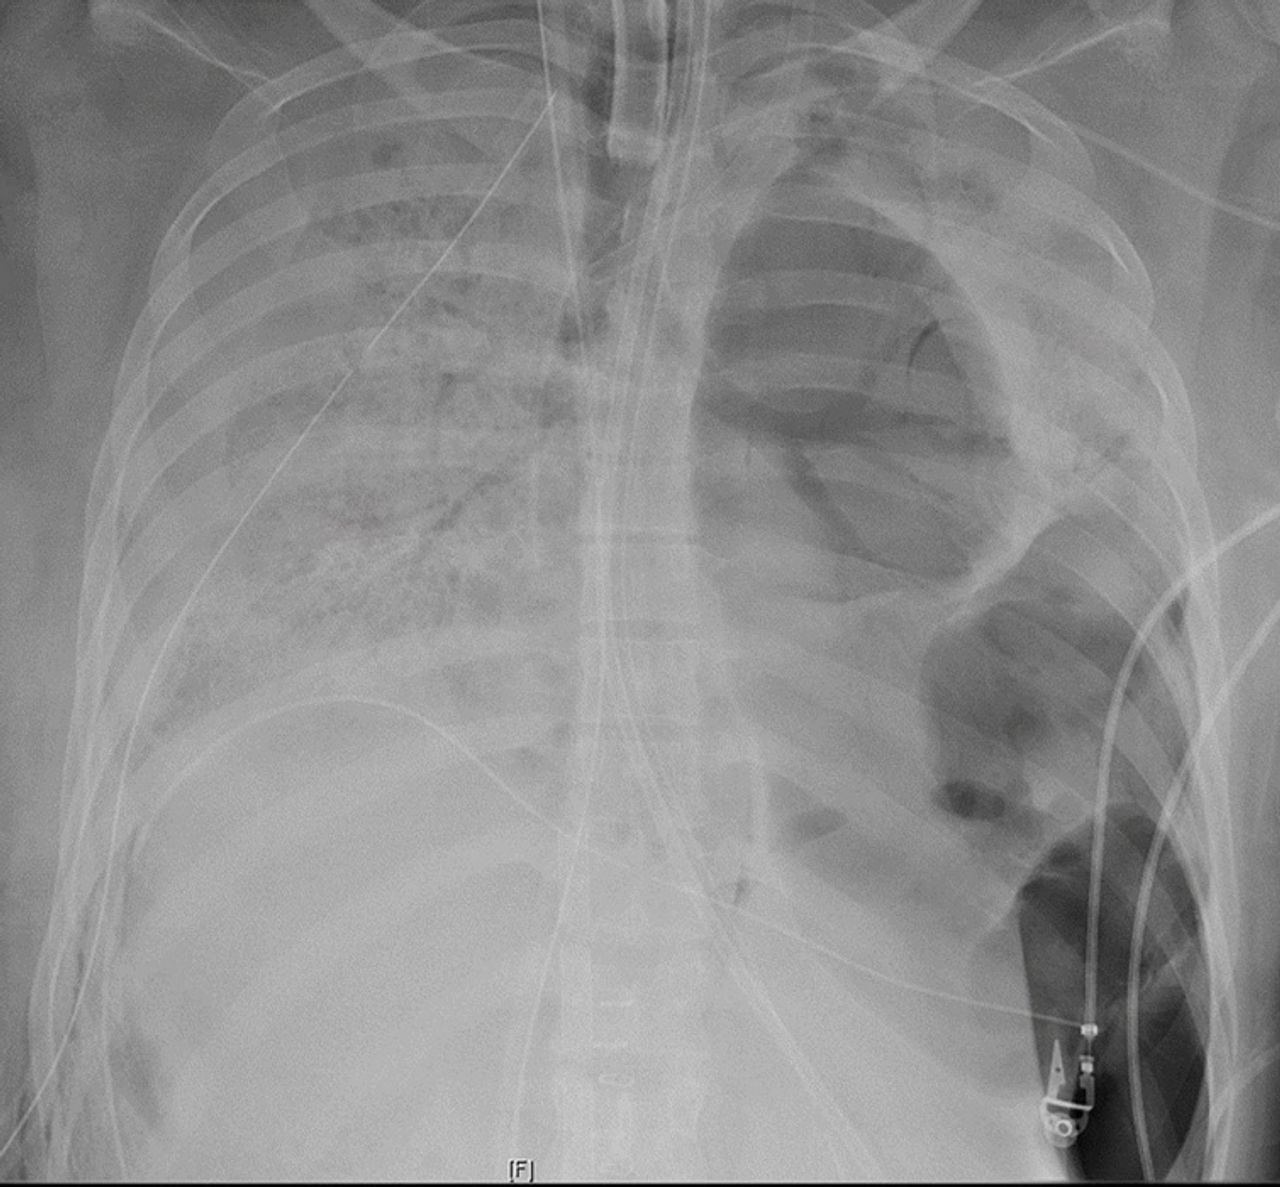

โรงพยาบาลนอร์ธเวสเทิร์น เมมโมเรียล เผยแพร่ภาพเอกซ์เรย์ปอดของผู้ป่วยรายนี้ที่ได้รับความเสียหายจากเชื้อโควิด-19